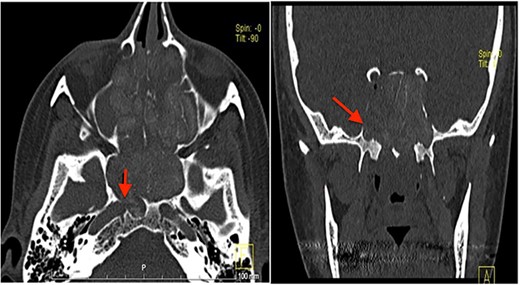

Computed tomography (CT) scan showed complete bilateral heterogenic opacification of paranasal sinuses, suggestive of chronic AFRS (Fig. 1). More importantly, there was some dehiscence of the lateral wall of the right sphenoid sinus near the petrous segment of the right ICA (Fig. 1). Having no previous history of head injury, trauma or surgical interventions, the existence for any aneurysmal carotid artery was not thought of.

CT scan, left imaging is an axial view, without contrast, showing complete opacification of all paranasal sinuses with heterogeneous density inside the sinuses; with erosion in the distal part of the right petrous carotid canal abutting the right sphenoid sinus (arrow); right image is a coronal view, showing extensive polyposis with bony erosion in the bony boundaries of the sphenoid sinuses.